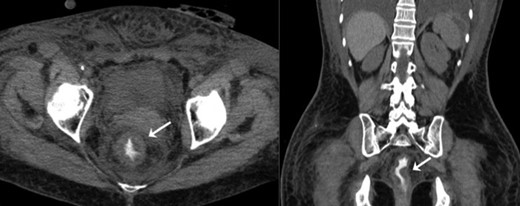

After 72 h of inotropic support with vasopressors, aggressive volemic resuscitation, ventilator support and antibiotics, a modest improvement was noted. WBC count decreased slightly from 30 000 to 23 000/μL. A repeat abdominopelvic CT scan was performed four days after the transfer and revealed once again the presence of a circumferential thickening of the rectosigmoid colon without pneumatosis (Fig. 1). The state of shock subsided gradually and the patient was extubated after a total of 9 days of ventilator support. She was transferred to the floor before being discharged from the hospital a few days later. She recovered progressively from the intensive care unit myopathy and the prolonged intubation, and benefited afterward from intensive rehabilitation.